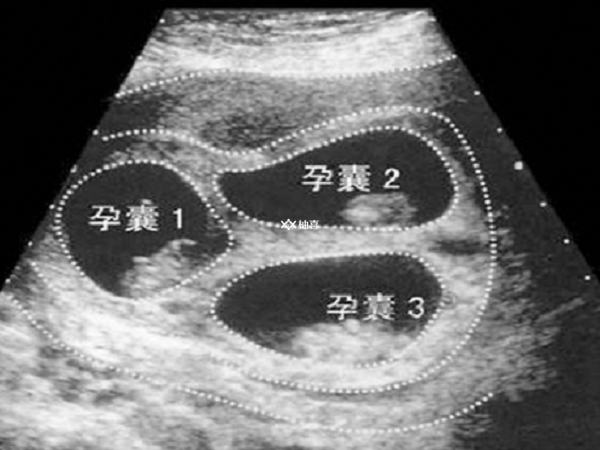

在胚胎移植过程中,如果移植多个胚胎,非常容易出现多胎妊娠。多胎妊娠会增加孕妇孕期的各种并发症风险,如妊娠期高血压疾病,其发生率是单胎妊娠的数倍。孕妇可能出现血压升高、蛋白尿、水肿等症状,严重的会引起子痫,危及母婴生命。同时,多胎妊娠还会增加孕妇患妊娠期糖尿病的风险,因为多个胎儿需要更多的营养,孕妇身体的代谢负担加重。